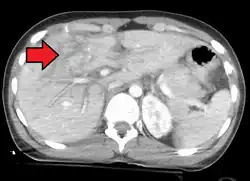

Imaging, such as the use of ultrasound or a computed tomography scan, is the generally preferred way of diagnosis as it is more accurate and is sensitive to bleeding, however; due to logistics this is not always possible.[6] For a person who is hemodynamically unstable a focused assessment with sonography for trauma (FAST) scan may take place which is used to find free floating fluid in the right upper quadrant and left lower quadrant of the abdomen. The FAST scan however may not be indicated in those who are obese and those with subcutaneous emphysema.[7] Its speed and sensitivity to injuries resulting in 400mL of free-floating fluid make it a valuable tool in the evaluation of unstable persons. Computed tomography is another diagnostic study which can be performed, but typically is only used in those who are hemodynamically stable.[7] A physical examination may be used but is typically inaccurate in blunt trauma, unlike in penetrating trauma where the trajectory the projectile took can be followed digitally.[8] A diagnostic peritoneal lavage (DPL) may also be utilized but has limited application as it is hard to determine the origin of the bleeding.[9] A diagnostic peritoneal lavage is generally discouraged when FAST is available as it is invasive and non-specific.[7]